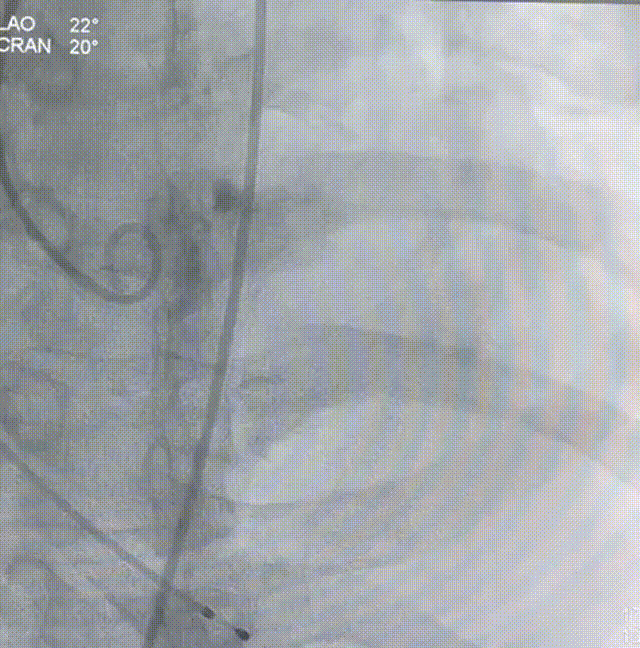

主动脉根部造影

22mm球囊预扩